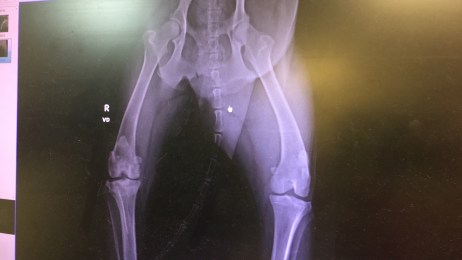

As I walked back with our Vet, Eddie, I felt my body go numb. We stood in front of the computer staring at images on the computer of Abe’s knee and hips. He informed me it was his ACL that had torn and he also had a fractured pelvis from an injury (I am not certain how he got.) Arthritis was beginning to form in his bones and Eddie confirmed what we had suspected, Abe would need surgery. Abe cried from behind his pen as he watched me look at the x-rays. My heart broke as we discussed options, referrals and cost of procedures.